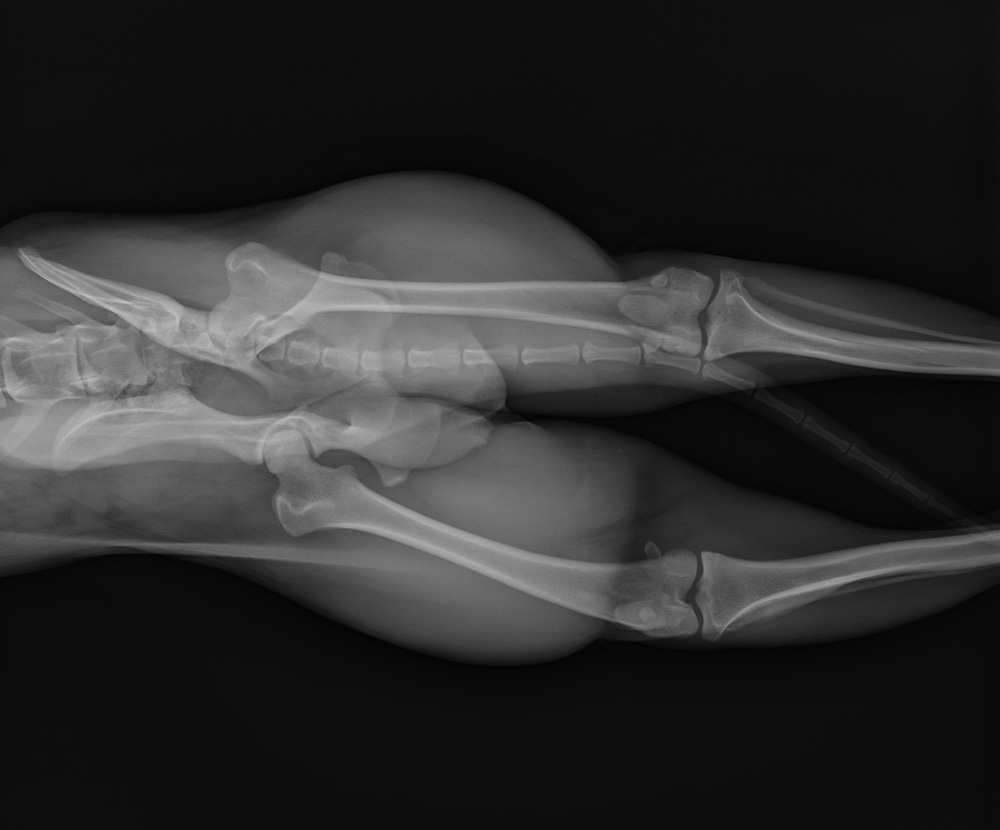

The series focuses on more complicated orthopaedic presentations, particularly the theory, decision making and execution of advanced fracture repair, joint injury and instability as well as the use of corrective osteotomies to restore limb alignment and joint function. The series covers joint disease and considers various therapies including newer opinions for its treatment, regenerative medicine and non-surgical therapies.

Practical videos will demonstrate the approach to most joints with a view to exploration, reduction and stabilisation of both minor and major joints. The videos examine salvage procedures like arthrodesis and then evaluate repairs, discussing the strengths and weaknesses of each. This will help anticipate potential complications, allowing you to modify outcomes and improve future cases.